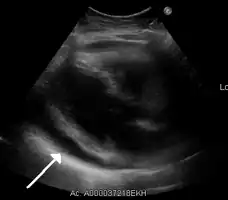

| A 2D transthoracic echocardiogram of a massive pericardial effusion. The "swinging" heart | |

A very large hemorrhagic pericardial effusion due to malignancy as seen on ultrasound. closed arrow: the heart, open arrow: the effusion